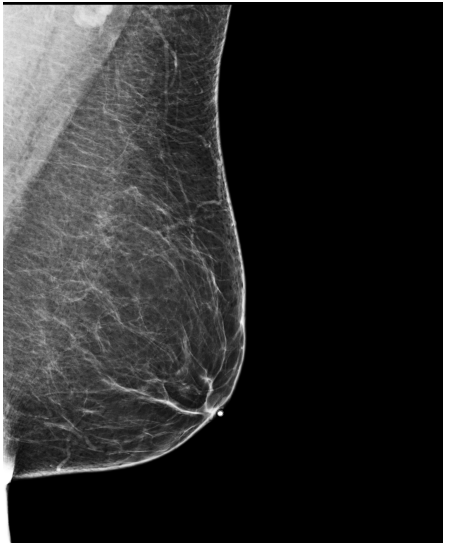

4.3 Pre-processing

The EMBED and CSAW-CC datasets originally consist of images in DICOM format, which are converted into 16-bit grayscale PNG images for consistency and compatibility. Following the pre-processing procedure outlined in (Yala et al.,, 2021), we enhanced image quality and removed background artifacts—such as textual annotations commonly present in mammography images—by applying a contour detection procedure. All contours in the image are detected, and only the largest contour, corresponding to the breast tissue, is retained. This contour is then used to create a mask that isolates the breast region from the background. The isolated breast image is resized to a size of 1664×20481664\times 2048 pixels while preserving the aspect ratio. Finally, the resized image is normalized and converted to a 16-bit format.

Following (Wang et al.,, 2024), we included only patients with at least five years of follow-up data for risk prediction. The datasets are randomly split at the patient level into training, validation, and test sets in a 5:2:3 ratio. Table1 presents the distribution of the Time-to-Cancer label and the dataset split for both the EMBED and CSAW-CC datasets.